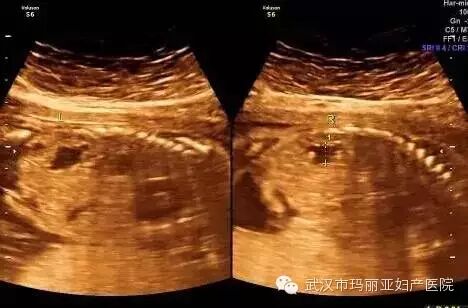

武汉玛丽亚妇产医院引进的世界领先的美国GE-E8四维彩超设备室目前世界上最先进、分辨率最高的彩色超声设备,具有即时立体成像、清晰准确的特点。

它能够多方位、多角度地观察宫内胎儿的生长发育情况,为早期诊断胎儿先天性体表畸形和发育异常提供科学依据。还能对胎儿的体表进行检查,如唇裂、脊柱裂、大脑、肾、 骨骼发育不良等,以便尽早的进行治疗。

玛丽亚美国GE-E8四维彩超排畸成功案例